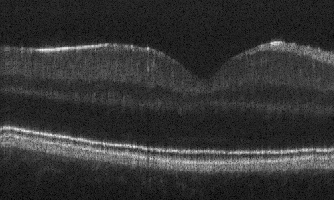

4.2 Comparison to baseline denoising model

Hu et al. [8] present a pseudo-modality fusion network (PMFN) that improves the feature preservation compared to a former method developed by Devalla et al. [7]. We use the PMFN as the baseline in this study. In Fig. 3, we observe that the retinal layers are more homogeneous in our proposed approach than in PMFN for all input SNR levels. Downstream analysis tasks such as layer segmentation would likely benefit from this improvement. We also note that small features like vessels are not sacrificed, even though other regions of the layers become denoised. To quantitatively confirm these observations, we use the average of 5 repeated frames (5-mean) as the reference ground truth image and we report several metrics in Table 1. Comparing with PMFN, the proposed method improve the denoising performance in terms of SNR, CNR and ENL. The results are significantly different in a paired, two-tailed t-test with a significance threshold of 0.05.